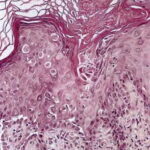

Histopathology. Focal acantholysis and dyskeratosis (focal acantholytic dyskeratosis) are present. Because these foci are small, they are sometimes found only when serial sections are obtained. The acantholysis may occur in four histologic patterns, resembling Darier’s disease , Hailey-Hailey disease, pemphigus vulgaris, or spongiotic dermatitis. Two or more of these patterns may be found in the same specimen. There is usually a superficial dermal infiltrate of lymphocytes and sometimes eosinophils. |

Ultrastructural Study. In the pemphigus-like zones, there is intradesmosomal separation, fewer desmosomes, and perinuclear aggregation of tonofilament bundles. In the Darier type, features similar to those of Darier’s disease are present. |